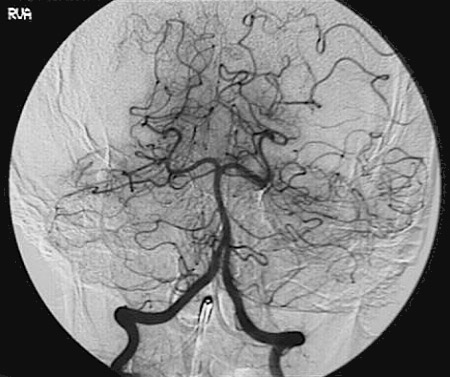

Identify the following arteries in the cerebral angiogram in the image above: Vertebral Artery - Basilar Artery